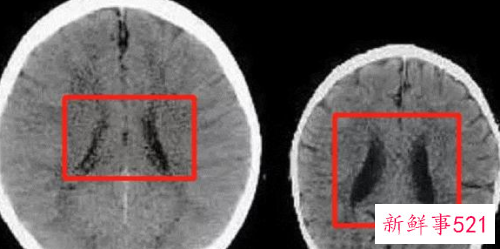

科学家曾做过一项研究,经过长期跟踪扫描两个3岁大孩子的大脑图形,观察他们大脑发育的差异,结果发现:

其中一个孩子的爸爸妈妈性格温柔,遇到事情会很有耐心的和孩子沟通,几乎没有打骂的经历;而另一个孩子的爸爸妈妈性格暴躁,不仅和孩子之间的沟通很少,只要遇到点事情,不是骂就是打,心情不好的时候也会打孩子。

两个同龄的孩子,在不同家庭环境下长大,大脑的发育也大相径庭。

左图是被温柔以待的孩子,右图是经常被打骂的孩子。

神经学专家解释,大脑中的黑色区域越大(如右图),就意味着孩子的脑容量越少,智商就会越低。